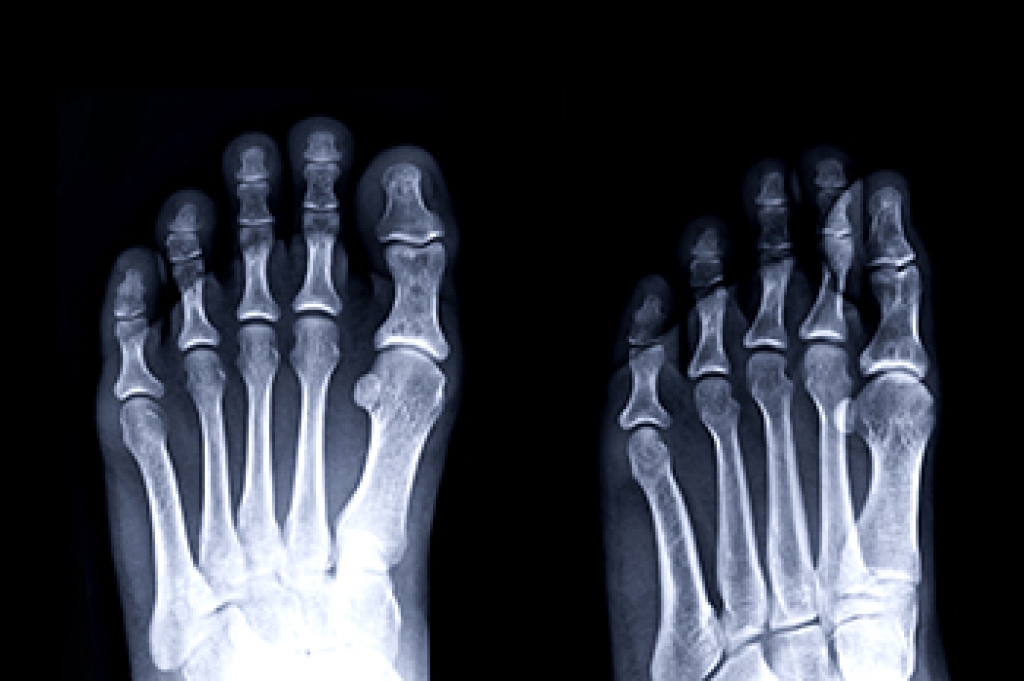

Poor Circulation in the Feet

Poor blood circulation in the feet and legs is can be caused by peripheral artery disease (PAD), which is the result of a buildup of plaque in the arteries.

Plaque buildup or atherosclerosis results from excess calcium and cholesterol in the bloodstream. This can restrict the amount of blood which can flow through the arteries. Poor blood circulation in the feet and legs are sometimes caused by inflammation in the blood vessels, known as vasculitis.